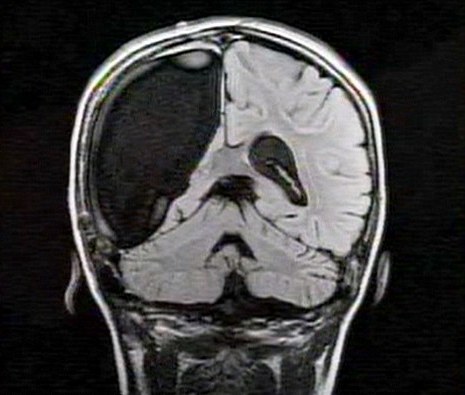

中新網(wǎng)3月26日電 據(jù)英國媒體26日報道,一名9歲的英國女孩在經(jīng)歷了右腦切除手術(shù)后奇跡康復(fù),令醫(yī)生和家人無比震驚。

報道稱,現(xiàn)年9歲的卡梅倫•莫特在手術(shù)中切除了她整個右半邊的大腦,而在經(jīng)歷如此重大的手術(shù)后能迅速康復(fù),莫特的奇跡也讓醫(yī)生和她的家人驚嘆不已。年幼的莫特也沒有因為病癥而放棄對夢想的追求。

卡梅倫莫特在3歲那年患上一種被稱作大腦功能紊亂“拉斯穆森”綜合癥,這種病癥誘發(fā)患者的無序暴力行為和嚴重的癲癇。醫(yī)生建議,治療這種病癥只能通過嘗試消除引發(fā)此癥狀的大腦組織。而手術(shù)讓莫特失去了幾乎整個半邊的大腦。

據(jù)悉,莫特在手術(shù)后已經(jīng)可以跑動和玩耍,她在術(shù)后的第四周離開了醫(yī)院。醫(yī)生表示,雖然右半邊大腦的切除可能會給莫特帶來半身不遂的風(fēng)險,但孩子剩余的大腦仍具有很強的重組和布線能力。